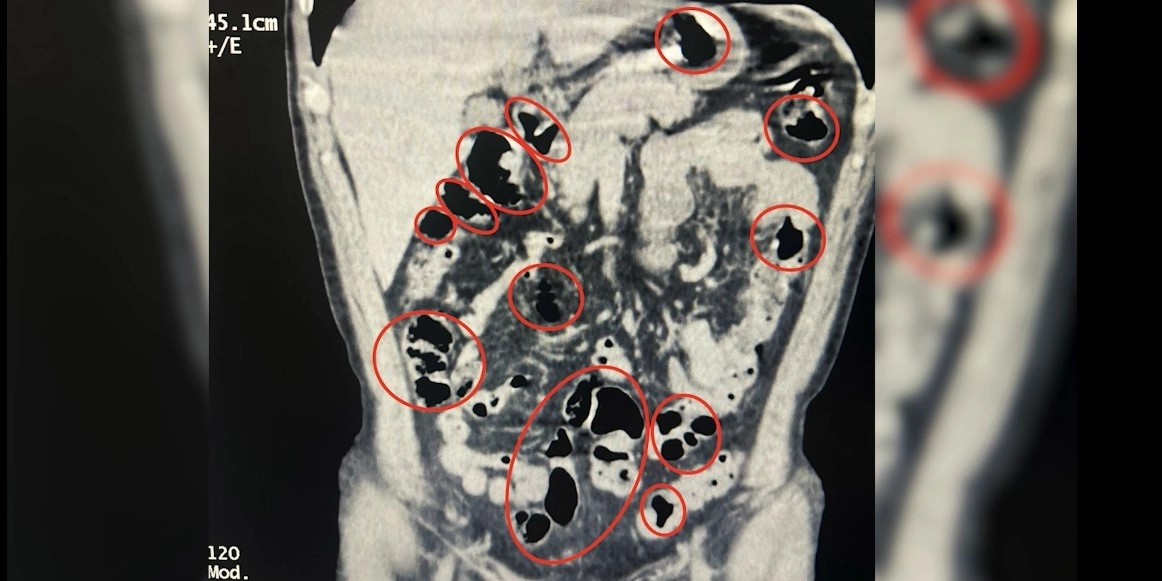

İl Emniyet Müdürlüğü Narkotik Suçlarla Mücadele Şube Müdürlüğü ile İstihbarat Şube Müdürlüğü ekiplerinin çalışması sonucu Tatvan ilçe girişinde durdurulan bir yolcu otobüsünde seyahat eden yabancı uyruklu 2 kişinin üzerinde arama yapıldı. Aramalarda şüphelilerin üzerinde 36 kapsül içerisinde uyuşturucu ele geçirildi. Tatvan Devlet Hastanesi’ne götürülen şüphelilerin burada yapılan röntgen ve tomografi incelemelerinde de mide ve bağırsaklarında yabancı cisimler tespit edildi. Tıbbi müdahale sonucu şüphelilerin yuttuğu 14 kapsül çıkarıldı. Toplam 50 kapsül halinde 385 gram metamfetamin ele geçirilen 2 şüpheli gözaltına alındı.